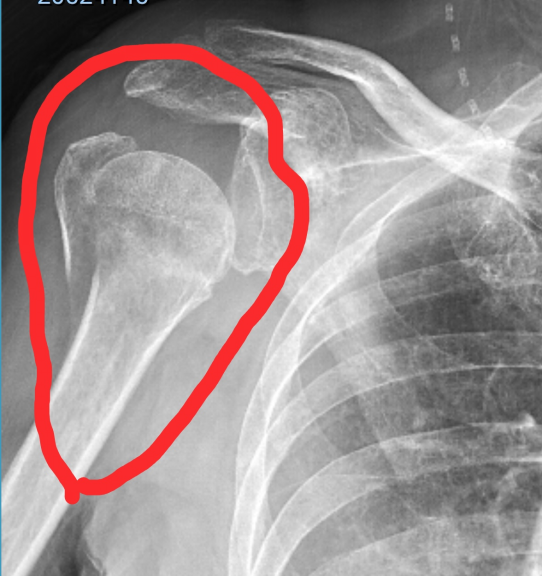

上图是该右肱骨近端粉碎性骨折伤者2026年2月1日18时在成都市郫都区某医院(三甲医院)作CT检查的图片。图片中见:肱骨头及肱骨外科颈部位有10多块碎骨影像,肱骨大结节骨折分离,肱骨干上段内下侧有条10cm多长的骨折线。

上图是:该右粉碎性骨折伤者2026年3月22日,在成都市郫都区某医院(三甲医院)拍的DR片图像;骨折对位良好,骨痂生长良好,骨折线模糊,仅见肱骨大结节骨折影像,右肱骨干上段内侧约10公分长的那条纵形骨折线消失了,肱骨头的骨折线及10多块碎骨均无明显影像。这是该粉碎性骨折已达到临床愈合标准的影像实证。